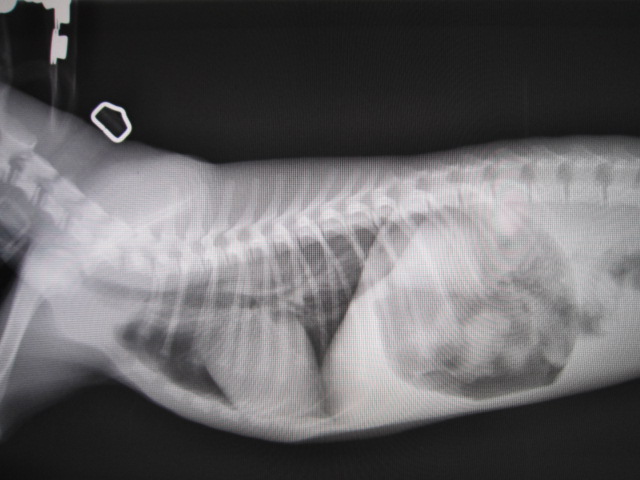

術前

術前のレントゲンです。

食道に異物があります。